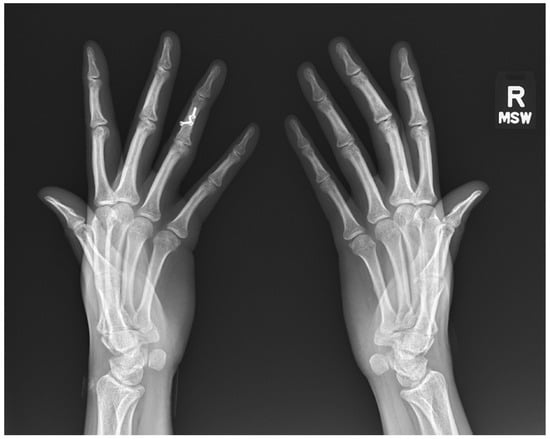

9. Systemic Lupus Erythematous (SLE)